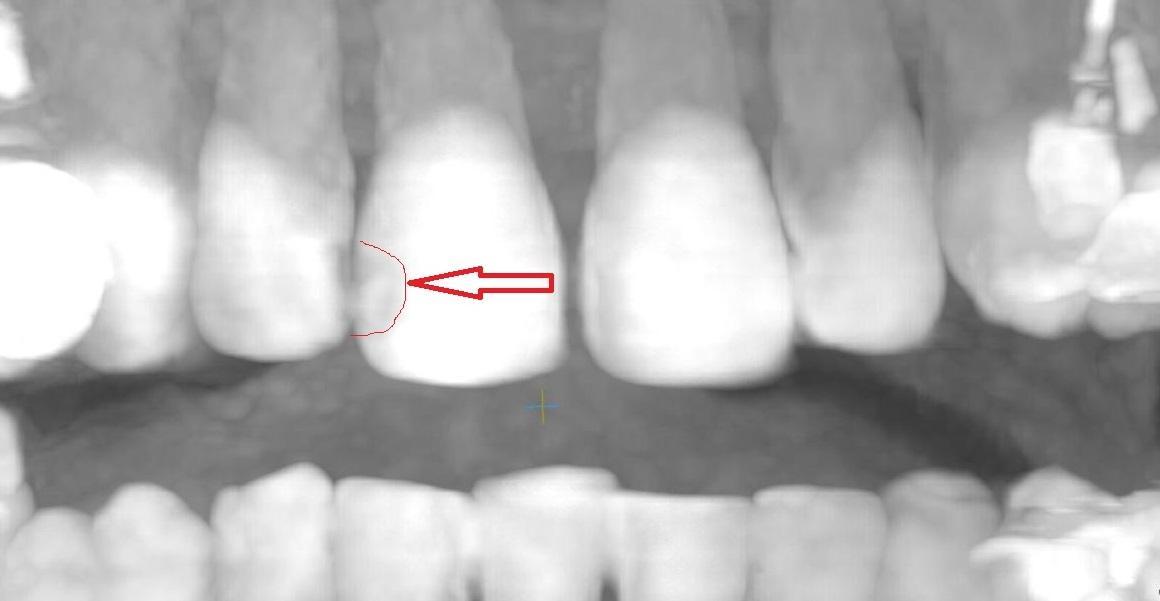

Юрий Жигурт, Подскажите, пожалуйста, есть ли кариес на 11 зубе (сторона контактная с 12 зубом)? Или его признаки. Если да, то насколько глубоко? Если возможно покажите, пожалуйста, стрелочкой где это наблюдается. Спасибо!

anastasiiia, есть основания предполагать: